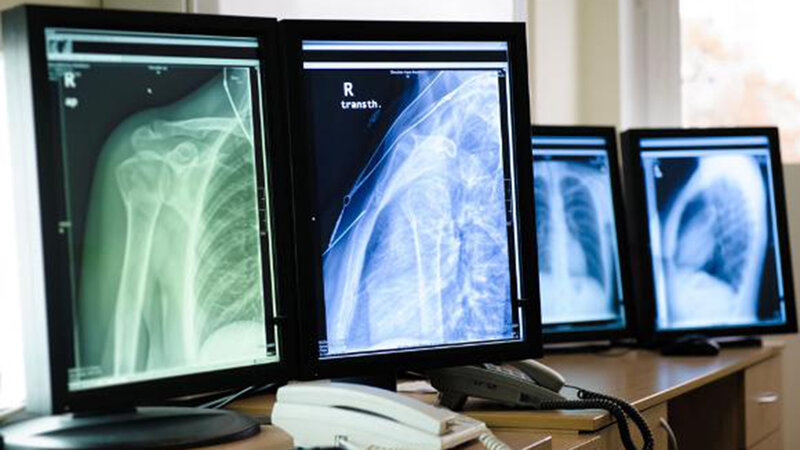

Das Belichtungspunktesystem und seine Bedeutung in der digitalen Radiographie (Teil 1)

Das Belichtungspunktesystem stellt in der Projektions-Radiographie ein Hilfsmittel zur geeigneten Auswahl der Expositionsparameter kV und mAs dar. Es dient primär der Vermeidung fehlbelichteter Aufnahmen, ist jedoch gleichzeitig sehr nützlich, um im Falle einer Fehlbelichtung deren Ausmaß abzuschätzen und ggf. zu kompensieren. Außerdem ermöglicht es die Umsetzung des ALARA-Prinzips, indem es dazu verhilft, das Profi l der Expositionsparameter nicht nur Aufnahmebedingungen, sondern auch einer Indikation anzupassen. In der DIN EN 62494-1 wird das Belichtungspunktesystem im Konzept des „Abweichungsindikators DI“ aufgenommen.